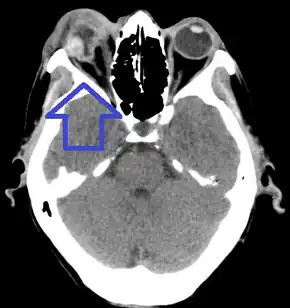

On CT scan, signs of global rupture include: deepening of the anterior chamber, alteration of global contour with scleral folds, discontinuity of scleral folds, and a shrunken globe.[6]